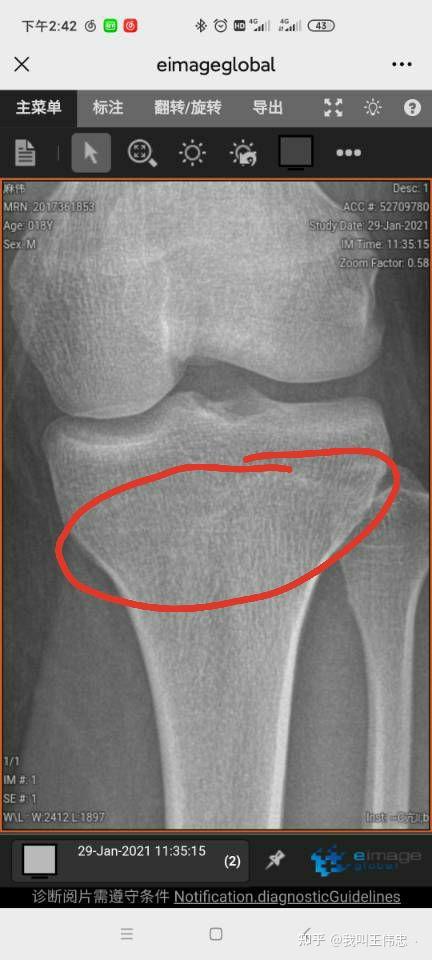

本人18,165。能否再长是需要去医院检查骨骺线的,也不贵100左右,我检查的时候是80的检查费25的咨询费,也不用怕丢人,直接问前台小姐姐,她会告诉你去哪挂号,挂什么科,检查什么(骨科-检查骨龄\骨密度)。

我原以为我还能长的,但是。